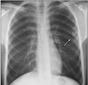

Karaciğer Lekeleri: Belirtileri ve TedavisiKaraciğer, vücudumuzun en büyük organlarından biri olup, birçok önemli işlevi bulunmaktadır. Karaciğer lekeleri, bu organ üzerinde meydana gelen anormal değişiklikler veya lezyonlardır. Bu lekeler, genellikle tesadüfen yapılan görüntüleme testleri sırasında fark edilir ve çeşitli nedenlerden kaynaklanabilir. Bu makalede, karaciğer lekelerinin belirtileri, nedenleri ve tedavi yöntemleri detaylı bir şekilde incelenecektir. Karaciğer Lekeleri Nedir?Karaciğer lekeleri, karaciğer dokusunda meydana gelen anormal hücresel büyümelerdir. Bu lezyonlar, iyi huylu (benign) veya kötü huylu (malign) olabilir. İyi huylu lezyonlar genellikle sağlık açısından tehdit oluşturmazken, kötü huylu lezyonlar kanserin bir belirtisi olabilir. Karaciğer Lekelerinin BelirtileriKaraciğer lekeleri genellikle belirti vermez, ancak bazı durumlarda aşağıdaki belirtiler görülebilir:

Karaciğer Lekelerinin TanısıKaraciğer lekelerinin tanısı genellikle aşağıdaki yöntemlerle yapılır: